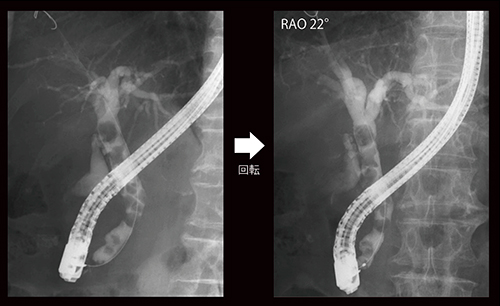

症例2は、胆道再建後の胆管腔腸吻合部狭窄の症例で、正面からでは左右肝管合流部や結石の同定が困難であるが、CアームをRAO30°回転させて左右肝管を視認できるようにすることで、結石を明瞭に描出できた(図7)。

図7 症例2:胆道再建後の胆管腔腸吻合部狭窄症例